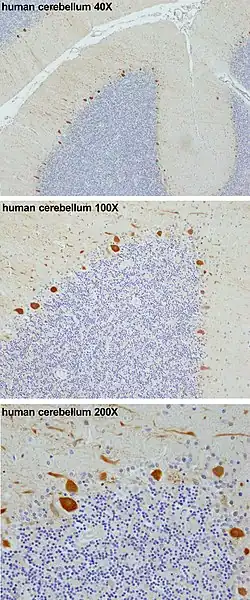

Korę móżdżku budują 3 warstwy. Najgłębiej leży gruba warstwa ziarnista, tworzona przez gęsto upakowane komórki ziarniste wraz z interneuronami, głównie Golgiego, ale też Lugaro i jednobiegunowe komórki szczoteczkowe. Pośrodku leży warstwa zwojowa (Purkiniego), wąska strefa zawierają perykariony komórek Purkiniego i komórek glejowych Bergmanna. Na wierzchu spoczywa warstwa drobinowa, zawierająca spłaszczone drzewa dendrytyczne komórek Purkiniego wraz z szeroką paletą włókien równoległych penetrujących drzewa dendrytyczne komórek Purkiniego pod kątem prostym. Najbardziej zewnętrzna warstwa kory móżdżku także zawiera dwa typy interneuronów hamujących: komórki gwiaździste i komórki koszyczkowe. Oba tworzą synapsy GABAergiczne na dendrytach komórek Purkiniego[9].

Komórki Purkiniego

Komórki Purkiniego należą do najbardziej wyróżniających się neuronów mózgowia oraz do najwcześniejszych rozpoznawanych. Opisał je po raz pierwszy czeski anatom Jan Evangelista Purkyně w 1837. Wyróżniają się kształtem drzewa dendrytycznego: dendryty rozgałęziają się bardzo obficie, lecz są silnie spłaszczone w płaszczyźnie prostopadłej do zakrętów móżdżku. Wobec tego dendryty komórki Purkiniego tworzą gęstą, a płaską sieć, przez którą przechodzą pod kątem prostym włókna prostopadłe[9]. Dendryty pokrywają kolce dendrytyczne, każdy z nich tworzy połączenie synaptyczne, którym odbiera informacje z włókna równoległego. Komórka Purkiniego odbiera więcej sygnałów wejściowych na swych synapsach, niż jakakolwiek inna komórka mózgu. Liczbę kolców dendrytycznych na pojedynczej komórce Purkiniego szacuje się na nawet 200 000[9]. Duże, okrągłe ciała komórek Purkiniego upakowane są w wąskiej (jednokomórkowej grubości) warstwie kory móżdżku, zwanej warstwą Purkiniego lub zwojową. Po odejściu kolaterali do okolicznych części kory jej aksony wędrują do jąder móżdżku, by tworzyć liczbę rzędu tysiąca połączeń każdy z kilkoma typami komórek jąder, wszystkimi w niewielkiej przestrzeni. Komórki Purkiniego wykorzystują jako neuroprzekaźnik GABA, wobec czego oddziałują hamująco[9].

Specyficzna, łatwo rozpoznawalna cecha komórek Purkiniego to ich ekspresja kalbindyny[21]. Barwienie na kalbindynę mózgu szczura po jednostronnym przewlekłym urazie nerwu kulszowego wskazuje, że komórki Purkiniego mogą na nowo powstawać w dorosłym już mózgu, rozpoczynając nową organizację płata móżdżku[22].